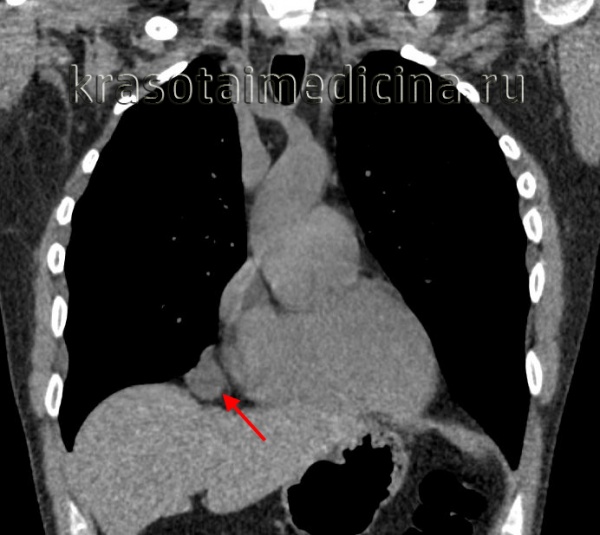

Бронхогенные кисты средостения

Встречаются в 30-35% наблюдений. Они также являются пороками эмбрионального развития и формируются из участков дистопированного бронхиального эпителия. Макроскопически представляют тонкостенные образования, заполненные прозрачной, реже бурой жидкостью. При гистологическом исследовании в них обнаруживается хрящевая ткань, соединительнотканные и гладкомышечные волокна слизистые железы.

Полость бронхогенной кисты средостения изнутри выстлана эпителием цилиндрического или реснитчатого типа. Внутри кисты содержится прозрачная или мутноватая желатинообразная, вязкая масса, которая, при наличии связи кисты с бронхиальным деревом, может нагнаиваться. Бронхогенные кисты средостения обычно располагаются позади бифуркации трахеи и тесно соприкасаются с трахеей или главными бронхами, иногда - пищеводом. Обычно они имеют однокамерное строение и достигают размеров 7-10 см в диаметре.